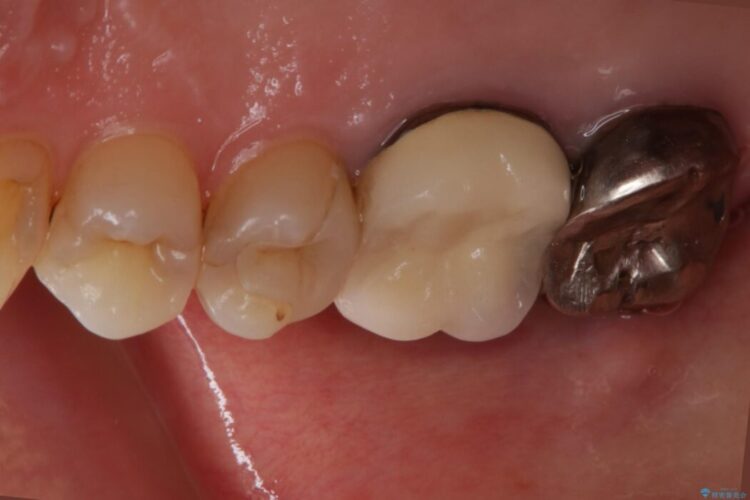

根管治療を再度行うことでフィステル(ニキビのようなできもの)は消失しました。

最終的にセラミッククラウンによる補綴治療を行いました。